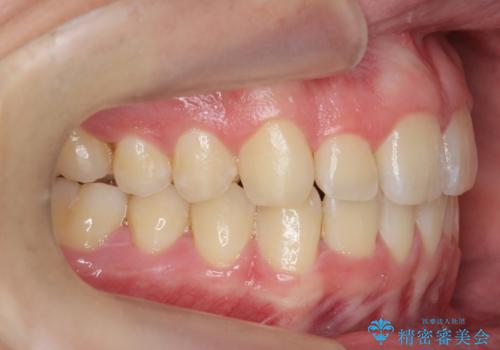

前歯のすき間、犬歯の異所萌出 乳歯を抜かずに矯正

- 前歯のすきまと八重歯を主訴に来院。

左上の乳犬歯が残っており、その下から生えてくるはずの犬歯(永久歯)が左上小臼歯部に萌出していました。

左上の乳犬歯は根もしっかりしていたため、

を提案し、➀を選択されました。

将来的にインプラントは希望されないとのことだったため、乳歯の部分は隙間を開けてインプラントを入れる用のすき間を確保するということは特に行いませんでした。

乳歯をそのまま並べたため、上顎の左右の犬歯の幅は非対称になっています。